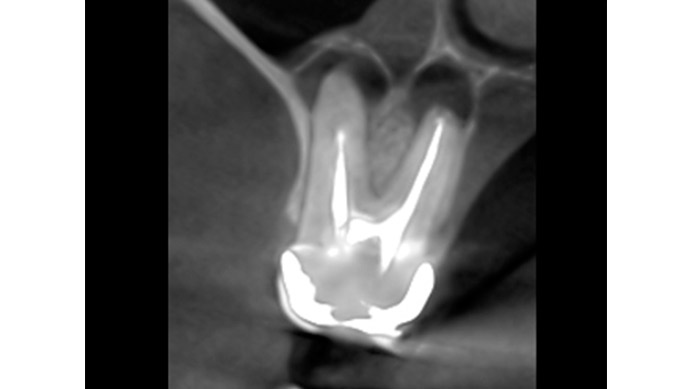

Ian es un paciente que nos cuenta su experiencia tras una intervención de cirugía periapical. Ian vino a la clínica dental IDIM con molestias en una muela superior que en el estudio radiográfico se vio que presentaba infección a causa del fracaso de una endodoncia.

Se decidió realizar una cirugía periapical para eliminar la infección y sellar las raíces con un empaste para evitar que volviera a tener problemas. Gracias a esta efectiva intervención Ian conserva su muela, lo cual es preferible, siempre que se puede, a tener que extraerla y sustituirla con un implante dental.